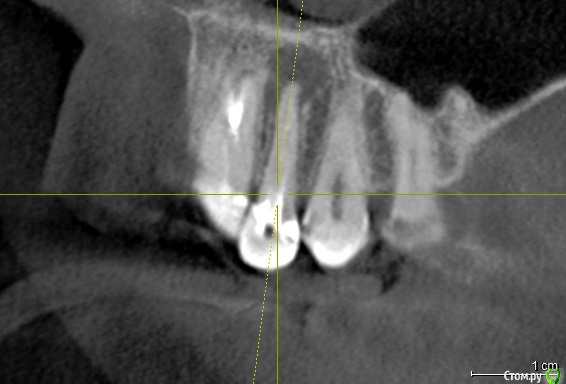

Ankazabolevshaya Опубликовано 28 мая, 2016 Поделиться Опубликовано 28 мая, 2016 Здравствуйте, уважаемые врачи! Очень сильно нуждаюсь в вашей помощи. В 2013 мне лечили два передних зуба (клык и передний). Пломбировали каналы, но коронки не ставили. Этой зимой я почувствовала боль в передних зубах в районе челюсти. Раздражение в дёснах. Резь. Потом вылез какой-то пупырь на десне. Я думала, что это стоматит. Не верила тем, кто мне говорил про нужность обзорного снимка. Признаю свою глупость. Теперь, после КТ оказалось что у меня сломаны эти каналы, а под левым клыком пустота. А пупырь, как мне сказали - это выход свища.Мне предложили зуб удалять. Как-то восстанавливать эту пустоту. Потом делать имплантацию. Есть ли сегодня технологии, позволяющие восстанавливать это пространство под зубом без его удаления, с последующей коронкой на него? И ещё один вопрос: могло ли все это случится из-за какой-нибудь заразы, занесенной во время лечения этих двух зубов в 2013г. ? Так же был момент ранения слизистой левой ноздри, как раз над свищем, который на десне. Просто очень часто слизистая иссыхала в одном месте и я травмировала слизистую. Буду очень благодарна за ответ. От меня в клинике ждут решения, а я переживаю, что улыбка испортится с искусственным зубом. Зуб этот свой очень люблю. Анна. Ссылка на комментарий

red_butler Опубликовано 28 мая, 2016 Поделиться Опубликовано 28 мая, 2016 Спасибо! Можете пояснить, Вы думаете, что зуб можно спасти? если судить только по снимкам, то да 1 Ссылка на комментарий

red_butler Опубликовано 29 мая, 2016 Поделиться Опубликовано 29 мая, 2016 а скажите, как по Вашему, это киста прикорневая? Или челюсть разрушена? Нужно восстановление челюсти? это не важно и корень ведь сломан, поставить под коронки всё равно можно? перелома не увидел И еще последнее, как Вы относитесь к процедуре - депофорез? В моём случае стоит в эту торону смотреть? бесполезно 2 Ссылка на комментарий